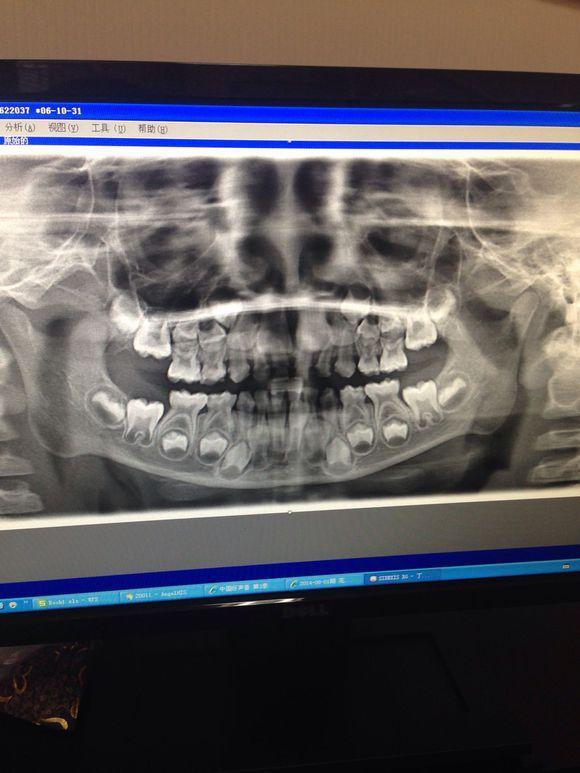

这是一个换牙期的颅骨,看起来确实有点让人难以接受。、

这是换牙期颅骨的侧面照,可以看出,如果宝宝乳牙未脱落,恒牙就长出,出现双层牙是多么恐怖是事情。